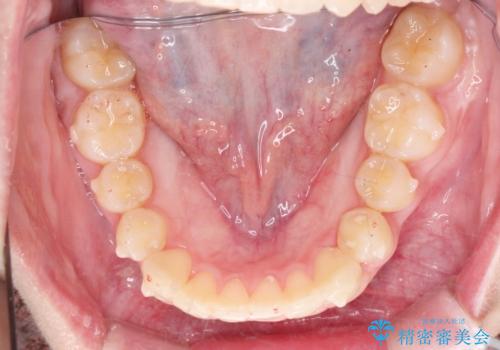

前歯のねじれをマウスピース矯正で治したい

- 前歯のねじれや がたつきを治したい、マウスピース矯正治療を希望され来院されました。

初診時程度のがたつきやねじれであれば、26枚以下のマウスピース矯正 モデレートプランで、比較的リーズナブルに矯正治療を受けていただくことができます。

実際の治療期間は約半年で仕上がりのような綺麗な歯並びを手に入れることができました。